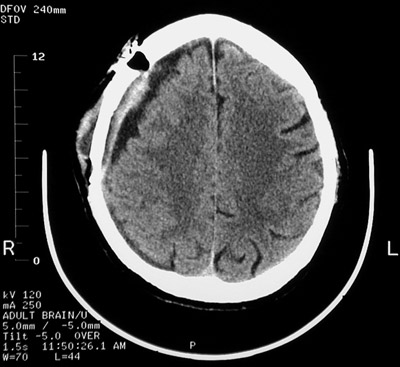

| A chronic subdural hematoma has been treated with evacuation of the organizing blood clot. The burr hole for the drain is drilled into the skull is seen on the right. In the view below of another case of chronic subdural hematoma following evacuation, the dark area near the hematoma on the left is air not yet resorbed following surgery. |